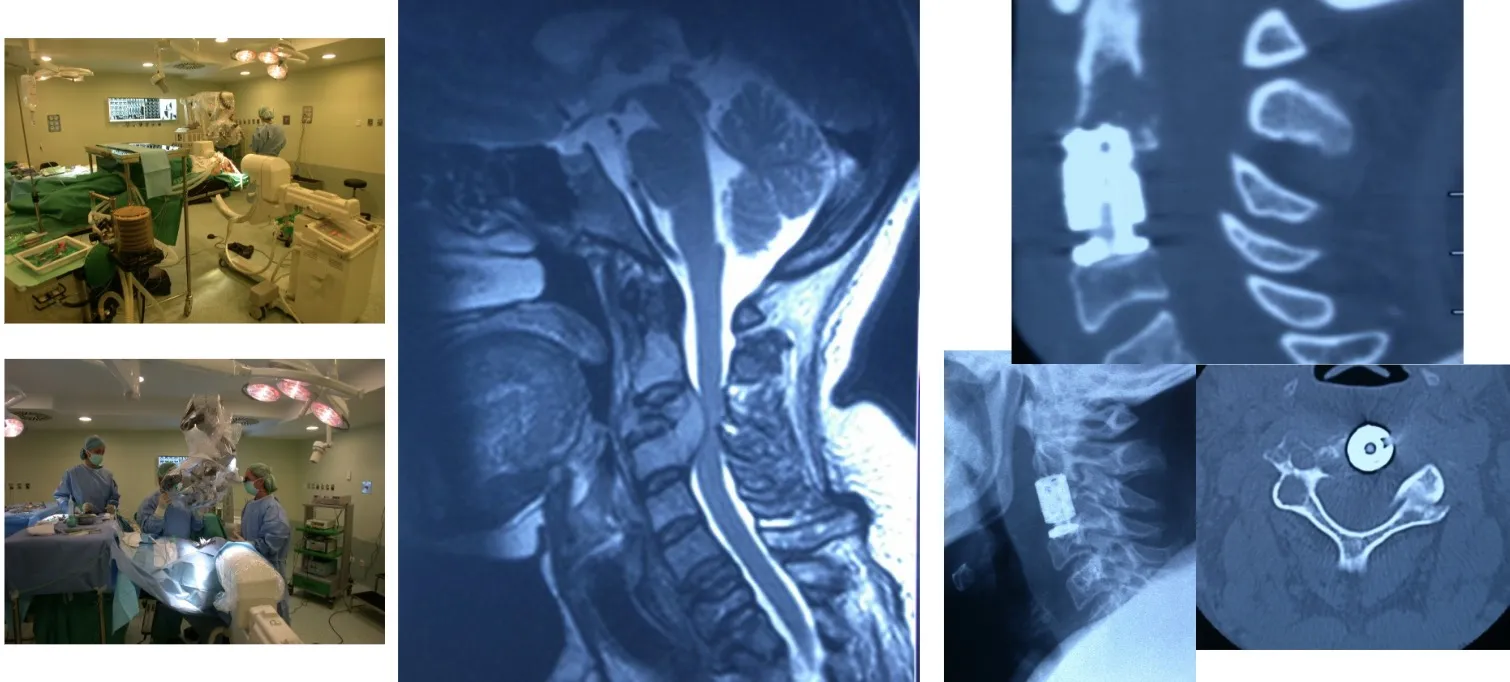

También es posible acceder a la columna cervical por vía anterior y resecar una vértebra completa cuando la lesión lo requiere. Este abordaje permite eliminar totalmente el cuerpo vertebral afectado, descomprimir la médula espinal y, posteriormente, reconstruir y estabilizar la zona mediante injertos óseos o dispositivos protésicos que restituyen la alineación y la función de la columna.

Otra opción es acceder por vía posterior, lo que permite realizar una fijación más sólida y estable mediante la colocación de tornillos y barras en los elementos posteriores de la columna. Este tipo de abordaje ofrece un mayor refuerzo estructural, especialmente útil cuando existe pérdida de sostén anterior o es necesario complementar una reconstrucción realizada previamente por vía anterior.

Si observamos la disposición de un quirófano moderno —independientemente del hospital en que se encuentre—, veremos que el paciente no está solo frente al cirujano, sino rodeado de un entorno de alta tecnología. Se trata de una coordinación precisa de numerosos equipos y sistemas que deben funcionar de manera perfectamente sincronizada.

Otro de los grandes avances tecnológicos, ya bastante conocido por muchos, es el neuronavegador. En el caso de la cirugía de columna, este sistema utiliza un TAC intraoperatorio obtenido mediante un equipo radiológico motorizado que rodea al paciente durante la intervención. A partir de esas imágenes, el cirujano dispone de una representación tridimensional precisa de la anatomía en tiempo real y puede orientarse con un margen de error inferior a un milímetro. De este modo, tanto en cirugía abierta como bajo microscopio, es posible conocer con exactitud la posición de los instrumentos y visualizar la estructura ósea y nerviosa del paciente en cada momento. Además, el sistema permite realizar controles intraoperatorios inmediatos, verificando el resultado antes de que el paciente abandone el quirófano.